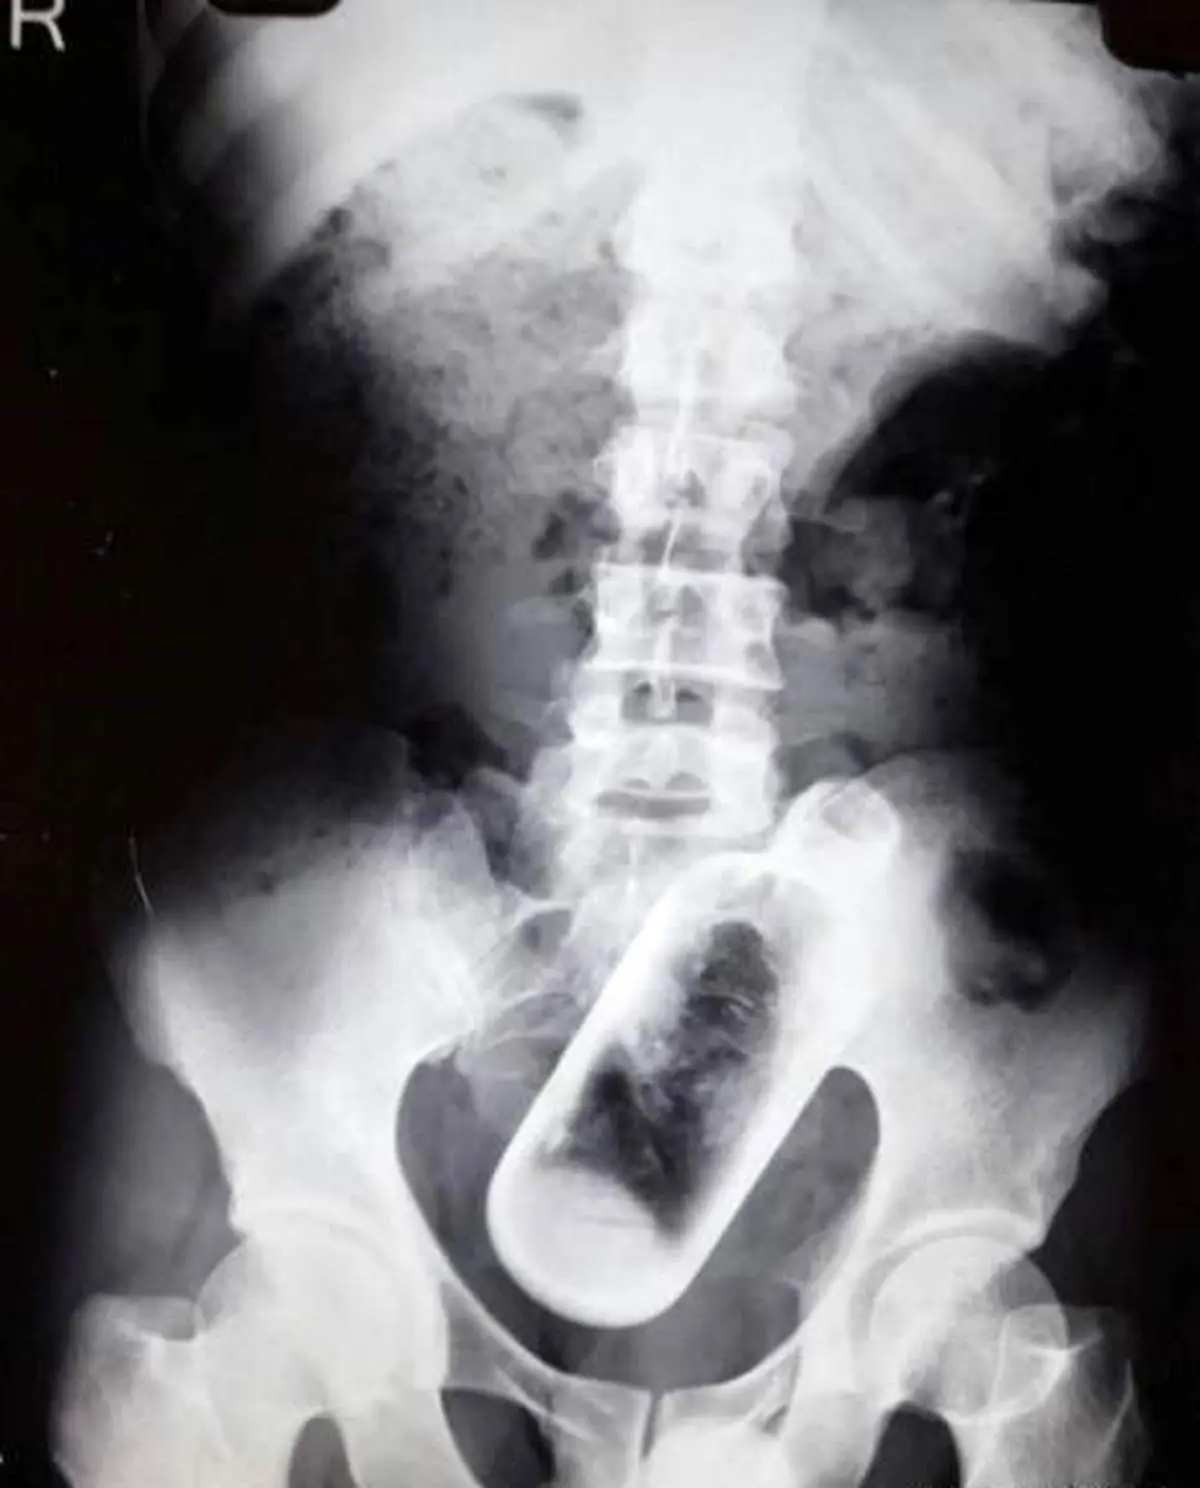

به گزارش منیبان؛ مردی که به دلیل دردهای شدید شکمی به بیمارستان مراجعه کرده بود با دیدن نتیجه سی تی اسکن حیرت زده شد، وجود یک بطری شیشه ای داخل بدن اش برایش غیر قابل باور بود تصاویری که پزشک را نیز از زنده ماندن این مرد در طول این مدت شگفت زده ساخت.

مرد 36 ساله که نالان از درد کمر و پشت به پزشک مراجعه کرده بود برای عکسبرداری به بیمارستان رفت تا علت اصلی تشخیص داده شود.

عکسبرداری انجام شد و وجود یک بطری شیشه ای 16 سانتی متری در بدن مرد محرض شد.

این مرد خبرساز می گوید :احتمالا زمانی که مست بودم این اتفاق افتاده است و ناخواسته بطری شیشه ای را قورت داده ام.

4 جراح متخصص بعد از 1.5 ساعت تلاش موفق شدند تا بطری شیشه ای را از شکم مرد خارج کنند. بطری داخل یک بسته قرار گرفت و برای آزمایشات دقیق تر به لابراتوآر بیمارستان فرستاده شد.

دکتر " گوپال سینگال" مسئول این جراحی می گوید :به جرات باید بگویم نه تنها من بلکه هیچ پزشکی در کشور هند شاهد چنین موردی نبوده است.